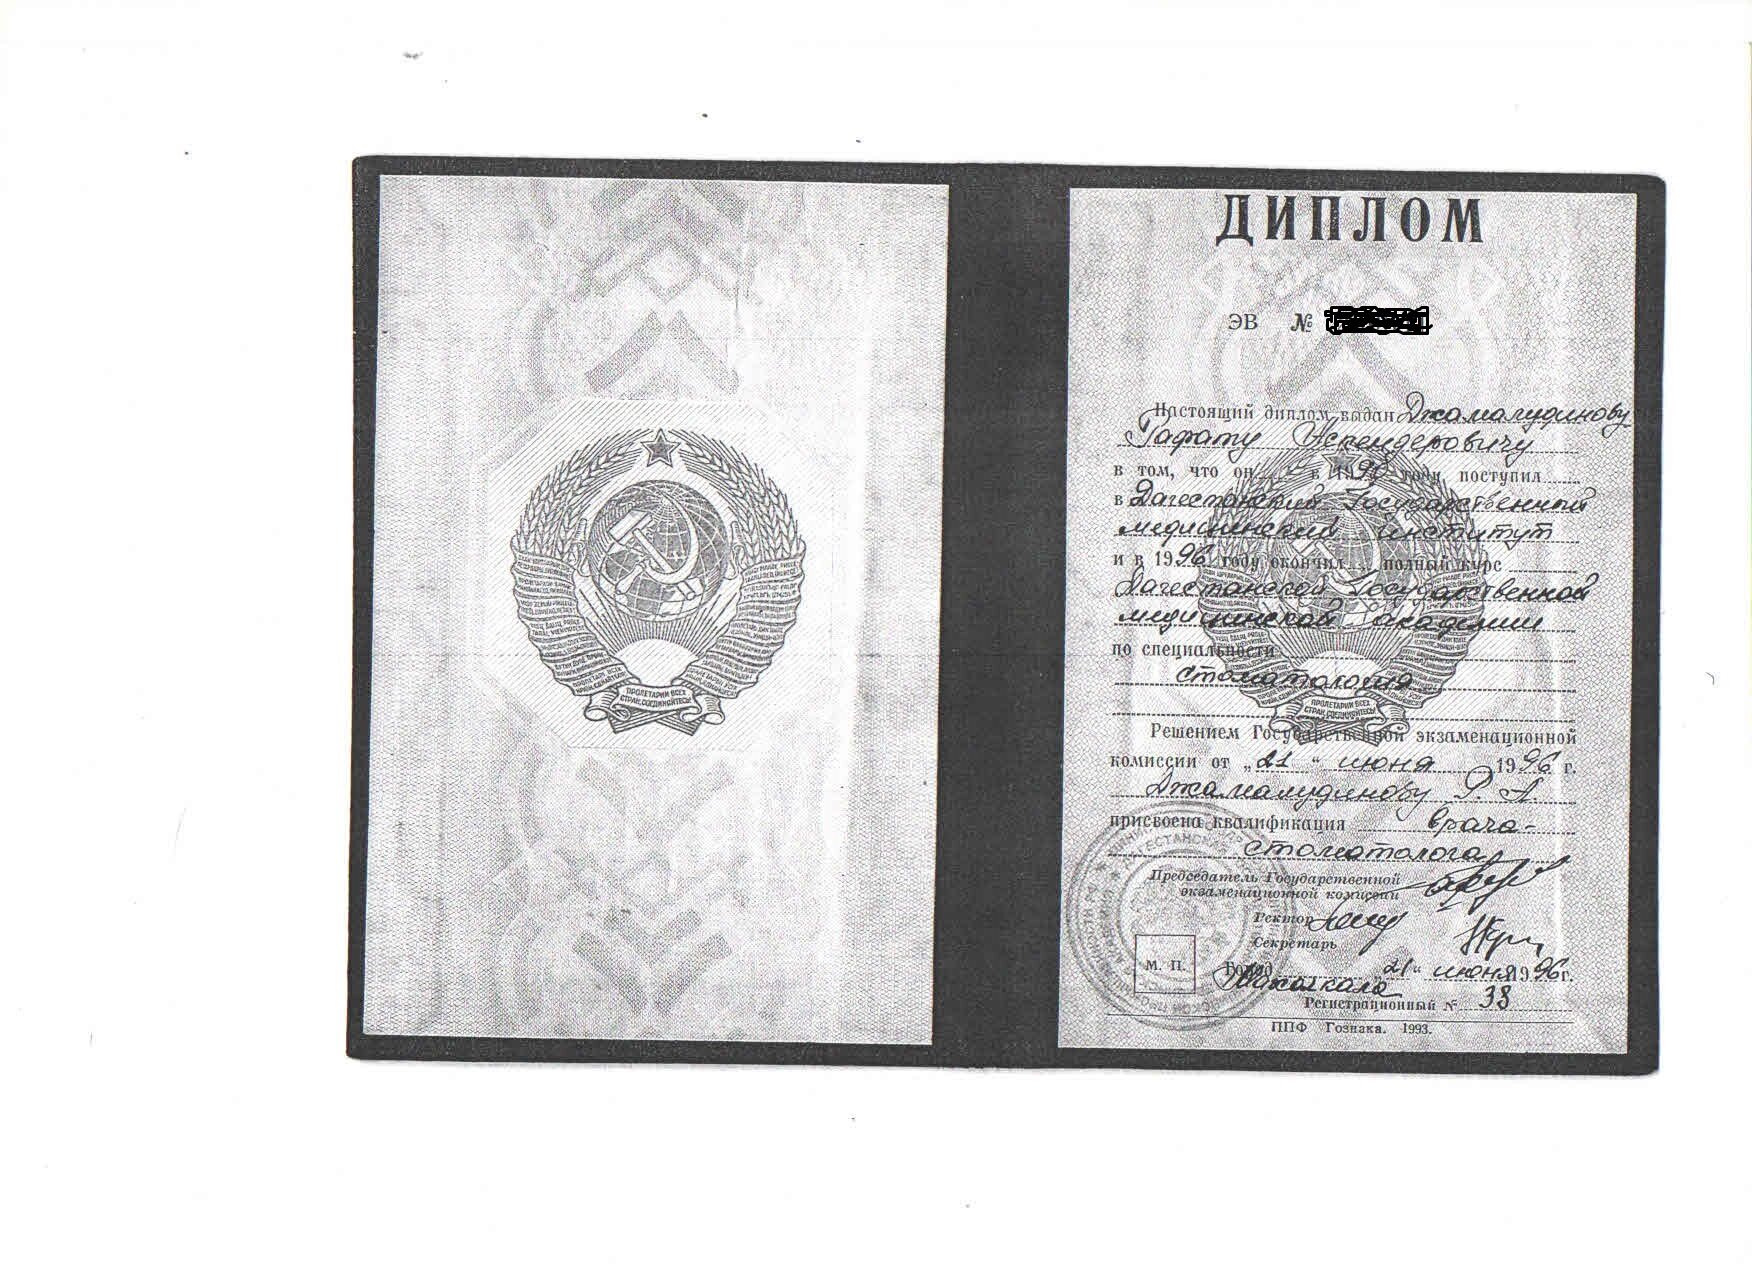

Джамалудинов Рафат Аскендерович является стоматологом-ортопедом, а также работает в сфере стоматологической хирургии. Рафат Джамалудинов в том числе проводит отбеливание зубов, реставрацию зубов, эндодонтическое лечение, реминерализирующую терапию зубов и профессиональную гигиену полости рта, обладает знаниями и навыками в области гнатологии, эстетической пародонтологии и эстетической реставрации зубов, а также устанавливает виниры, скайсы, металлокерамические и безметалловые протезы, вкладки, штифты и условно-съемные протезы.

Рафат Джамалудинов.